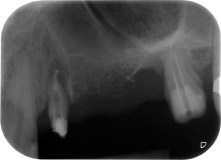

Fig. 1: 58-year-old patient. Preoperative radiograph showing an apical periodontal lesion at tooth 24 and horizontal loss of alveolar bone in the second quadrant.

A 58-year-old female patient complained of pain and increased mobility of her bridge abutment tooth 24. Periodontal inflammation was present with pocket depths of 7 mm mesiobuccally and more than 12 mm distally, as well as third-degree furcation involvement. Moreover, the radiograph revealed an extensive periodontal lesion around the apical region of the (alio loco) endodontically pretreated tooth 24 (Fig. 1).

One year earlier, teeth 25 and 26 had been extracted due to trauma and for endo-perio reasons, prior to the placement of the bridge. A combined endo-perio lesion was diagnosed for tooth 24, of unclear aetiology. The patient wanted to keep her bridge abutment teeth 24 and 27 and would not accept a final, or even temporary, removable prosthesis. Therefore, it was agreed to make all efforts to retain both teeth, in spite of their poor prognosis as based on radiological and clinical findings.